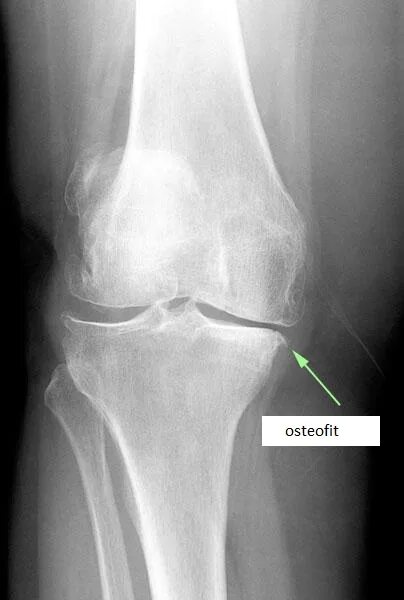

Остеофит причины